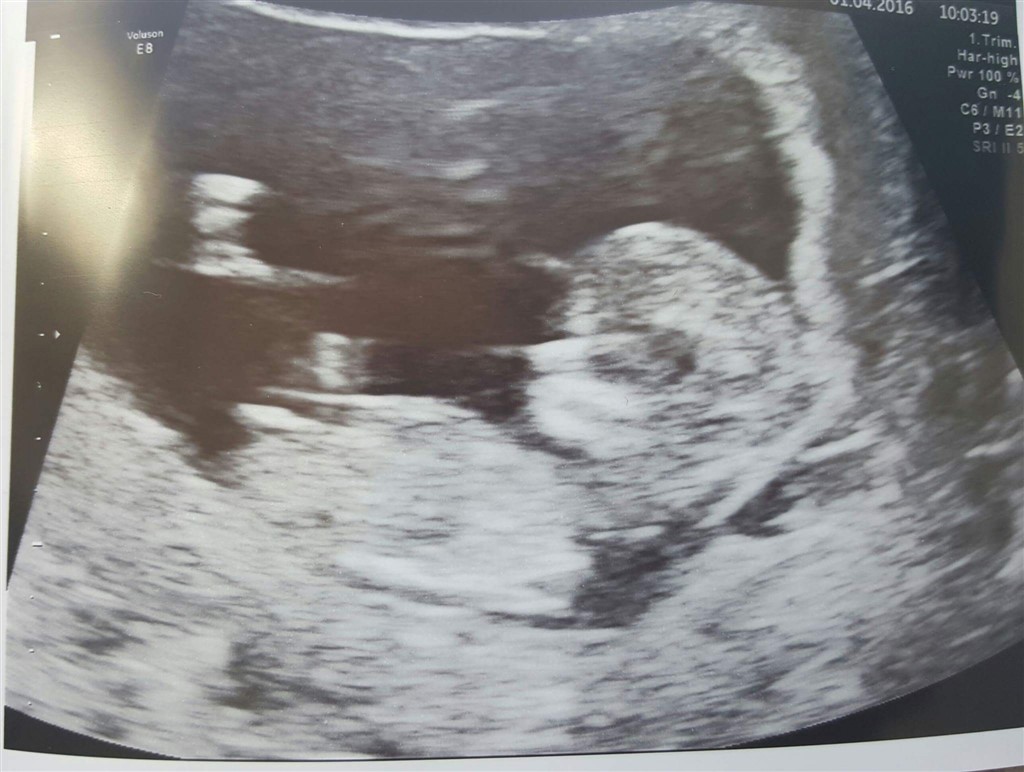

Ud fra dit scanningsbillede så siger nubben en pige da den ligger vandret

nu har jeg selv en pige og venter en dreng nu og dit billede ligner 100 % mit scannigsbillede fra min pige.. Scanningsbilledet fra min dreng er anderledes og der peger nubben mere op ad

der er også det der skull theory som siger at piger er mere flade i panden og drenge er buler lidt mere ud i panden og det har også passet på begge mine

ellers er der nogle der siger at piger generelt ligger med hovedet til højre side og drenge med hovedet mod venstre

dette har også passet på begge mine, men hvor meget hold der er i det ved jeg ikke